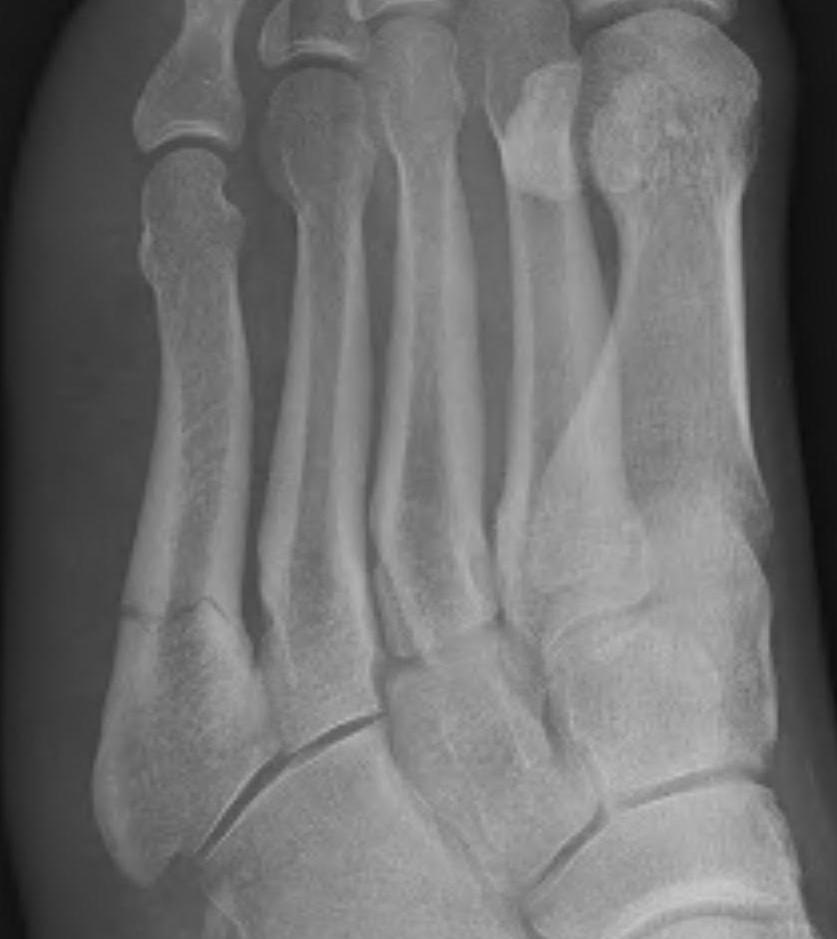

5th Metatarsal Shaft Fractures

Definition

Spiral fracture of the shaft of the 5th metatarsal

Dancer's fracture

Gonzalez et al Foot Ankle Spec 2024

- 37 spiral 5th metatarsal fractures

- 78% women, average age 50

Nonoperative management

- treated weight bear as tolerated

- all healed by 3 months

- 27% mild pain

- 3% significant pain